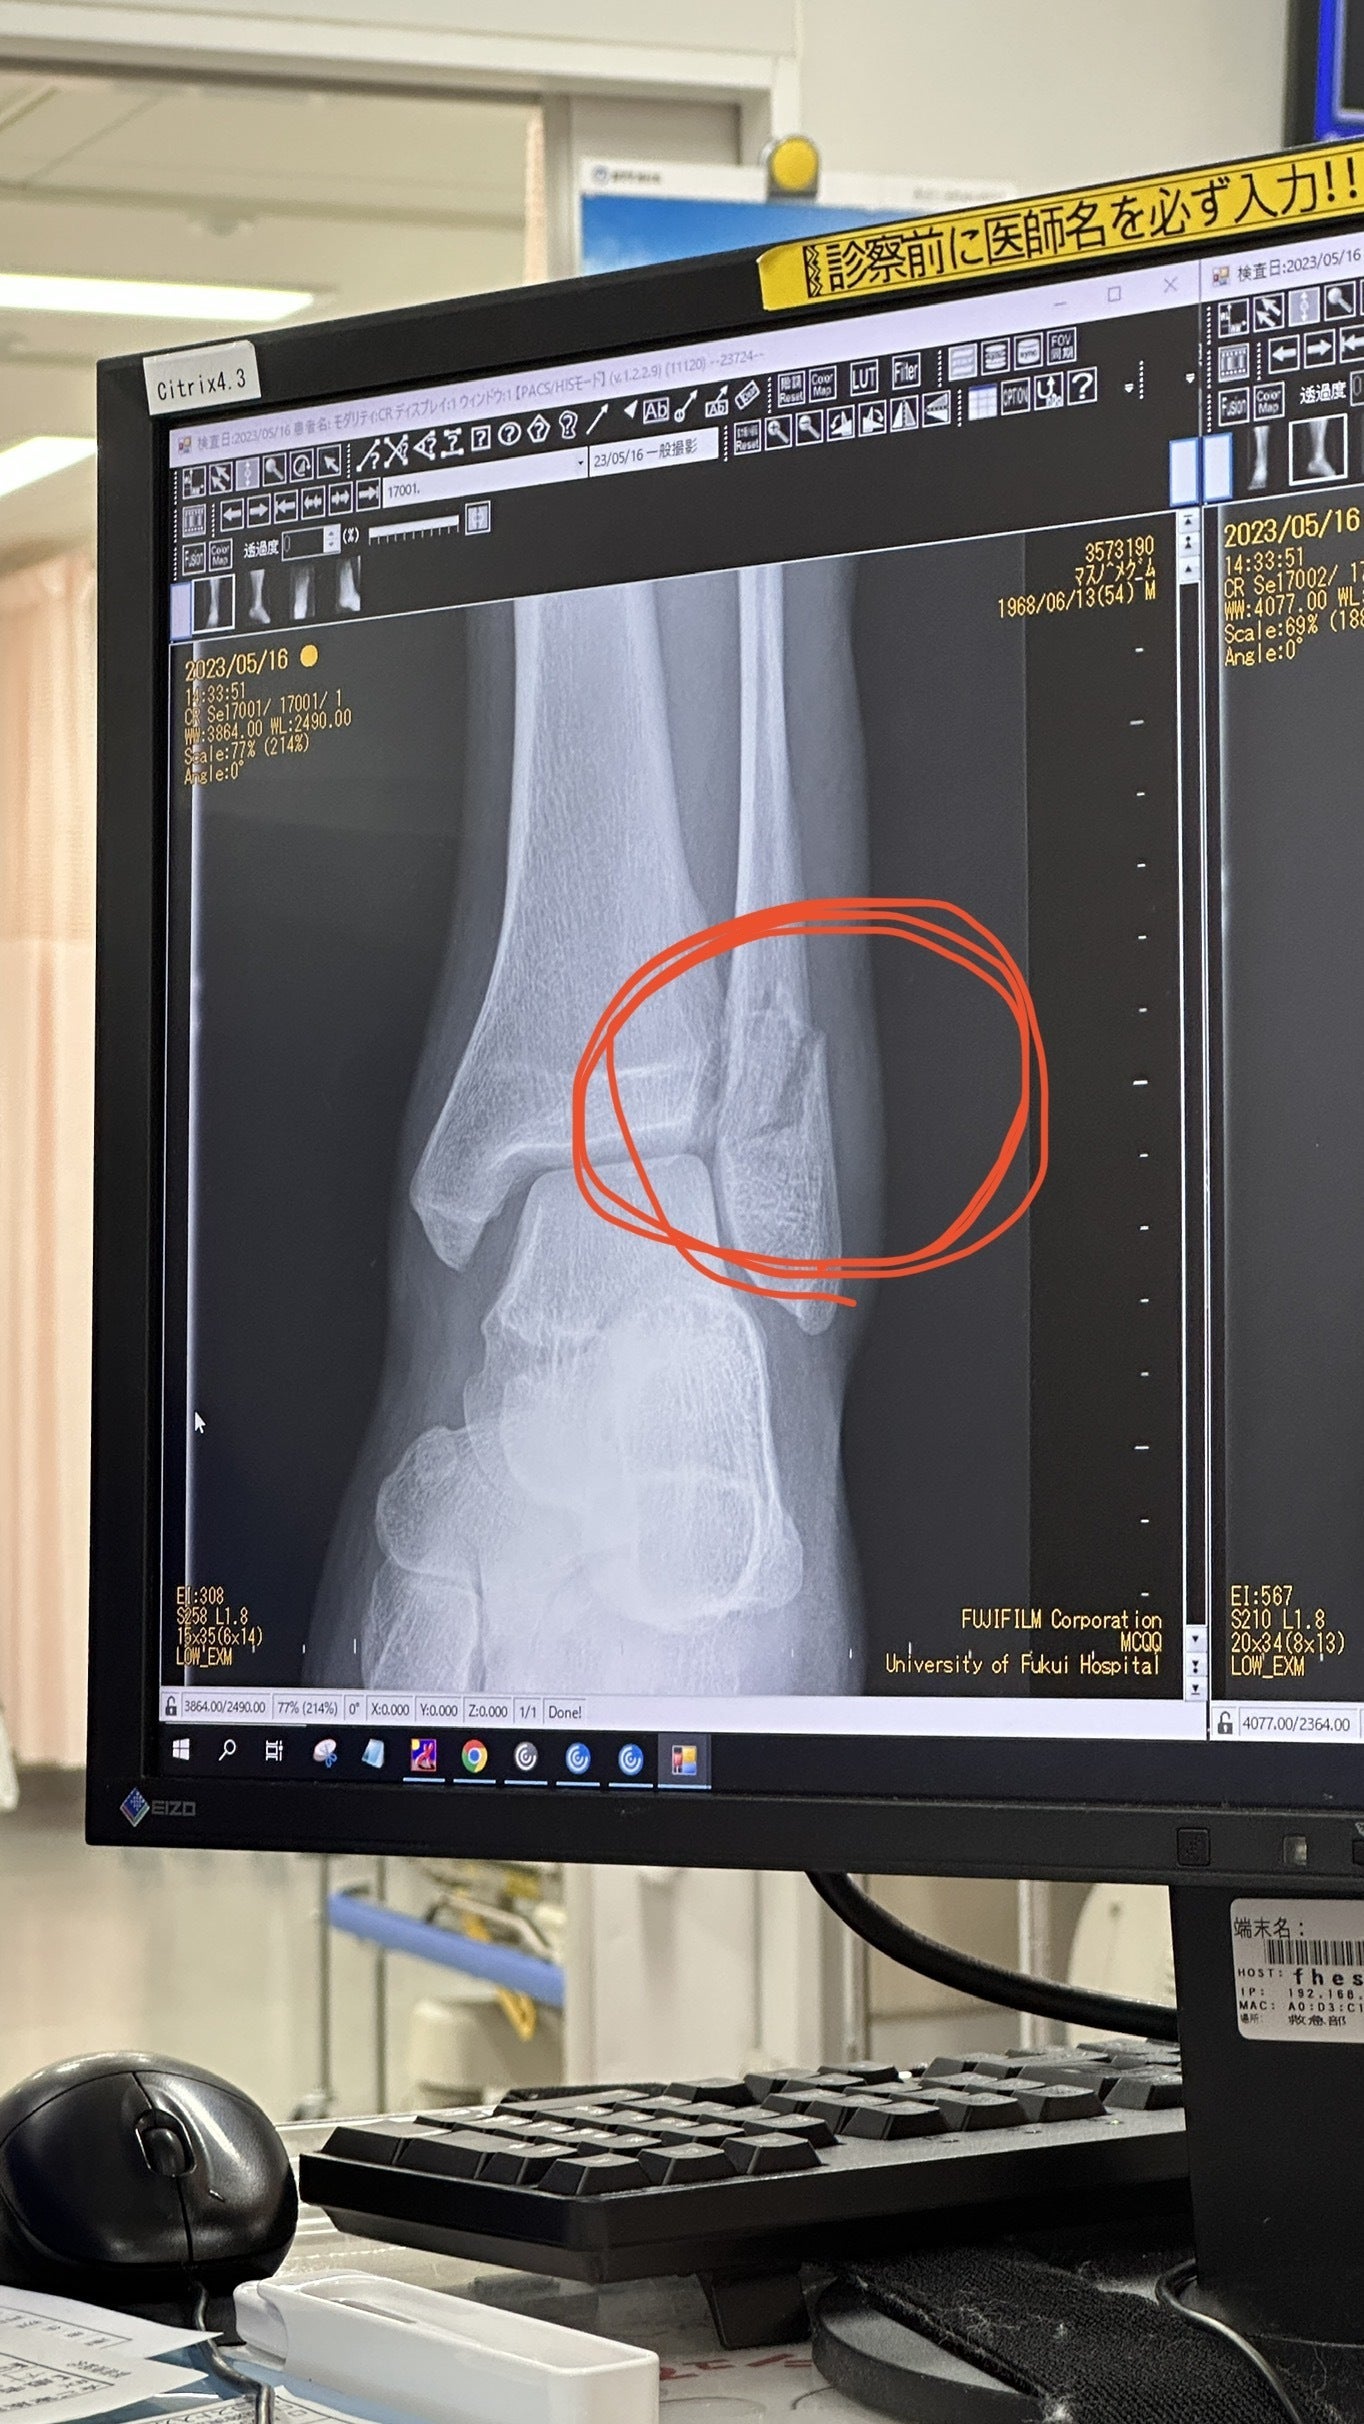

くるぶしを骨折

戻ってきてそのまま病院へ

手術の日程が決まり、今日から入院することになりました。